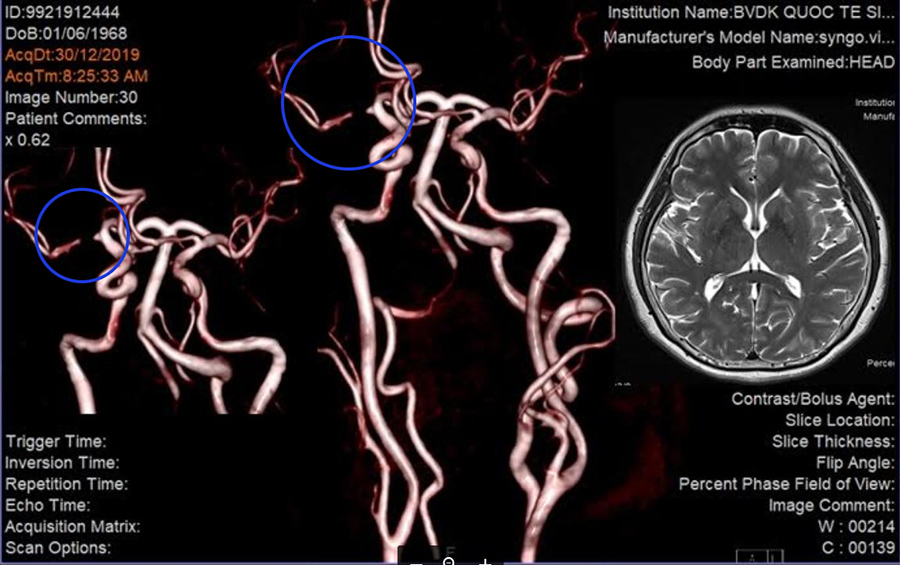

Dị dạng mạch máu não là hiện tượng các mạch máu bất thường, rối loạn trong não. Các dị dạng này nối thông động mạch và tĩnh mạch não mà không đi qua các mao mạch, không cung cấp máu cho nhu mô não. Các dị dạng mạch máu này khi vỡ gây chảy máu não. Đây là một căn bệnh bẩm sinh và hết sức nguy hiểm. Dị dạng mạch máu nào là những bất thường bẩm sinh phát triển từ tuần thứ tư đến tuần thứ tám của thai kỳ khiến động mạch thông nối trực tiếp với tĩnh mạch không qua mạng lưới mao mạch trung gian vì vậy, đa phần dị dạng mạch máu não có thể tồn tại lâu trong não mà không có bất kỳ triệu chứng gì. Tuy nhiên, nguyên nhân của dị dạng mạch máu não vẫn còn nhiều bàn cãi, có thể liên quan với nhiều yếu tố bao gồm cả tính di truyền và hoạt động kích thích sinh mạch (đây là một quá trình sinh lý, ở đó, những mạch máu mới hình thành từ những mạch máu sẵn có trước) có thể đóng vai trò quan trọng trong sự xuất hiện của dị dạng mạch máu.

Thường thì bệnh nhân dị dạng mạch máu não không có triệu chứng, chỉ được phát hiện tình cờ khi đang điều trị một bệnh lý không liên quan khác. Nhiều bệnh nhân nhập viện với biểu hiện biến chứng có chảy máu. Bệnh nhân mắc bệnh dị dạng mạch máu não thuộc nhóm 45 tuổi trở xuống và phát hiện khi bị chảy máu não, đau đầu, động kinh, hoặc tình cờ khi đi khám tầm soát. Ngày nay tỉ lệ bệnh nhân được chẩn đoán dị dạng mạch máu não tăng lên nhờ những tiến bộ trong kỹ thuật ghi hình không xâm nhập. Dị dạng mạch máu não có thể kích thích mô não chung quanh và gây ra số triệu chứng chủ yếu là cơn co giật mới khởi phát, yếu hoặc liệt cơ, mất phối hợp, khó khăn khi thực hiện những động tác phức tạp, chóng mặt, đau đầu. Ngoài ra, bệnh nhân có vấn đề về ngôn ngữ, các cảm giác bất thường như: tê, ngứa, đau tự phát...